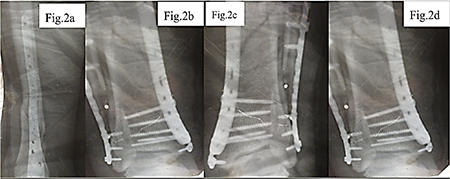

Initial postoperative period. The obtained data are shown in Figure 5. After the performed osteosynthesis, the patient was discharged for outpatient follow-up with drainage systems placed to control the outflow of postoperative exudate. In the first days after the surgery, moderately pronounced hyperemia and tenderness in the area of the postoperative wound were noted, requiring regular analgesia. The drainage tubes continued to produce serous-hemorrhagic exudate, in some cases with admixtures of purulent masses, which indicated the initial signs of an inflammatory reaction in the area of the surgical intervention. However, it should be noted that the formation of serous-hemorrhagic and cloudy (purulent-like in appearance) exudate in the postoperative wound area is a consequence of the cascade of local inflammatory processes that develop in response to surgical tissue damage and may not always be of precise bacterial origin [13, 14]. In the first hours after the intervention, activation of inflammatory mediators (histamine, prostaglandins, interleukins) causes vasodilation, increased microvascular permeability, and the release of plasma and cellular elements into the intercellular space, which leads to the accumulation of serous or serous-hemorrhagic exudate with admixtures of erythrocytes due to microvascular injury [13]. In the following days, under conditions of a pronounced local inflammatory reaction, active neutrophil migration to the wound begins [13-16]. Degradation of damaged tissues and phagocytosis of necrotic debris result in the formation of cloudy exudate with an increased content of proteins, leukocyte remnants, and cellular debris – this process is not necessarily associated with bacterial infection but is a typical manifestation of aseptic (sterile) inflammation at the wound-cleaning stage [13-16]. Only upon the addition of an infectious agent does the exudate acquire the classical features of infectious pus (with a strong odor, specific color change, massive leukocyte content, and bacteria on microscopy) [17]. Thus, cloudy purulent-like masses at the initial stages may be the result of aseptic inflammation, which is a natural stage of healing after significant tissue trauma.

Control radiography (Fig. 5 a, b) demonstrated complete consolidation of the fractures and formation of hypercallus as a marker of restored osteoblastic activity. This confirmed the reversibility of metal-induced immune osteopathy and the importance of correcting immune, vascular, and neurogenic disorders together with ensuring mechanical stability.